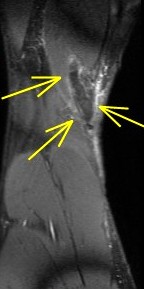

Figure 2 for case Semitendinosus tendon tear, retracted( RID2717 )

Figure 2